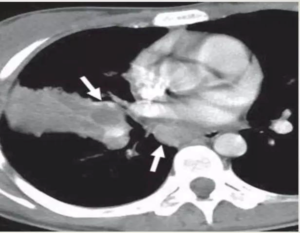

• Rasmussen aneurysm is a pseudoaneurysm that results from weakening of the pulmonary artery wall by adjacent cavitatory TB.

CECT obtained shows cavitatory consolidation with air-crescent sign in left upper lobe.